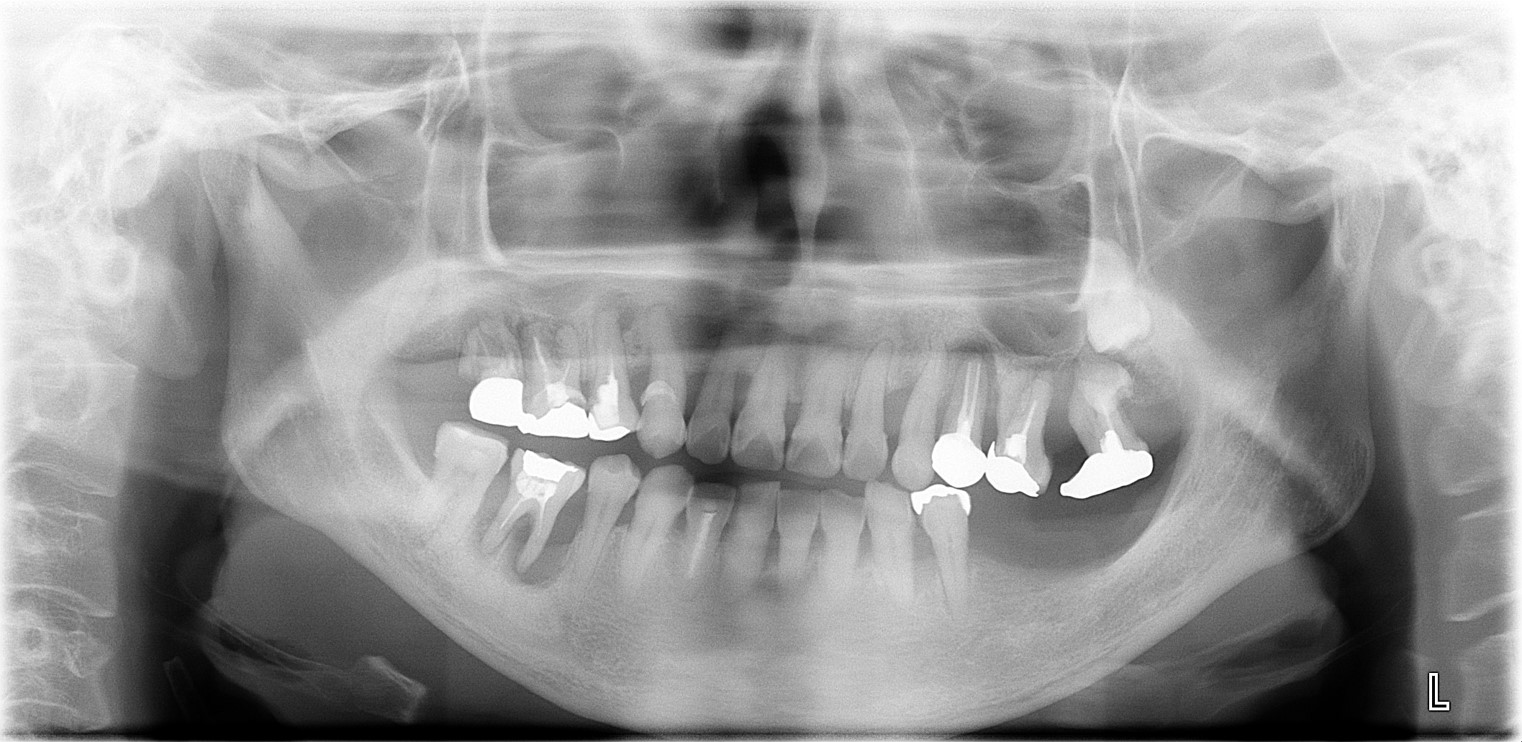

| 症状 | 重度の歯周病で来院され、痛みを訴えられた。 |

| 治療結果 | 審美的にも機能的にも良好になり、今後の全身疾患予防にも、見た目のアンチエイジングにも繋がった。

笑顔がより一層素敵になられた。 ※治療結果は患者様によって個人差があります。 |

| 治療方法 |

まず、プラークコントロール指導と徹底的な歯周病治療を行い、全身疾患との兼ね合いをしっかりと指導。 そこから、審美歯科と右側第一大臼歯1本インプラント治療へ。(歯列叢生のため数本抜歯しブリッジへ) 以前、他院で治療を中断されていたので、最後まで治療を継続されるようにコミュニケーションをしっかりとり、メインテナンスの重要性をしっかりとお伝えした。 |

| 治療費用(税込) |

前歯上下セラモメタルクラウン12本:1,584,000円(税込)

| 治療期間 | 2年6ヵ月 |

| メインテナンスの頻度 | 3ケ月毎 |

| 治療を行う上での注意点(リスク / 副作用) |

全身疾患は問題なく、オペもすすめられた。外科手術により、腫れや一時的に内出血を起こす場合がある事を伝えておく。 治療後、インプラントや補綴物を守るためにナイトガード装着。 メインテナンスの重要性をしっかりお伝えした。 |